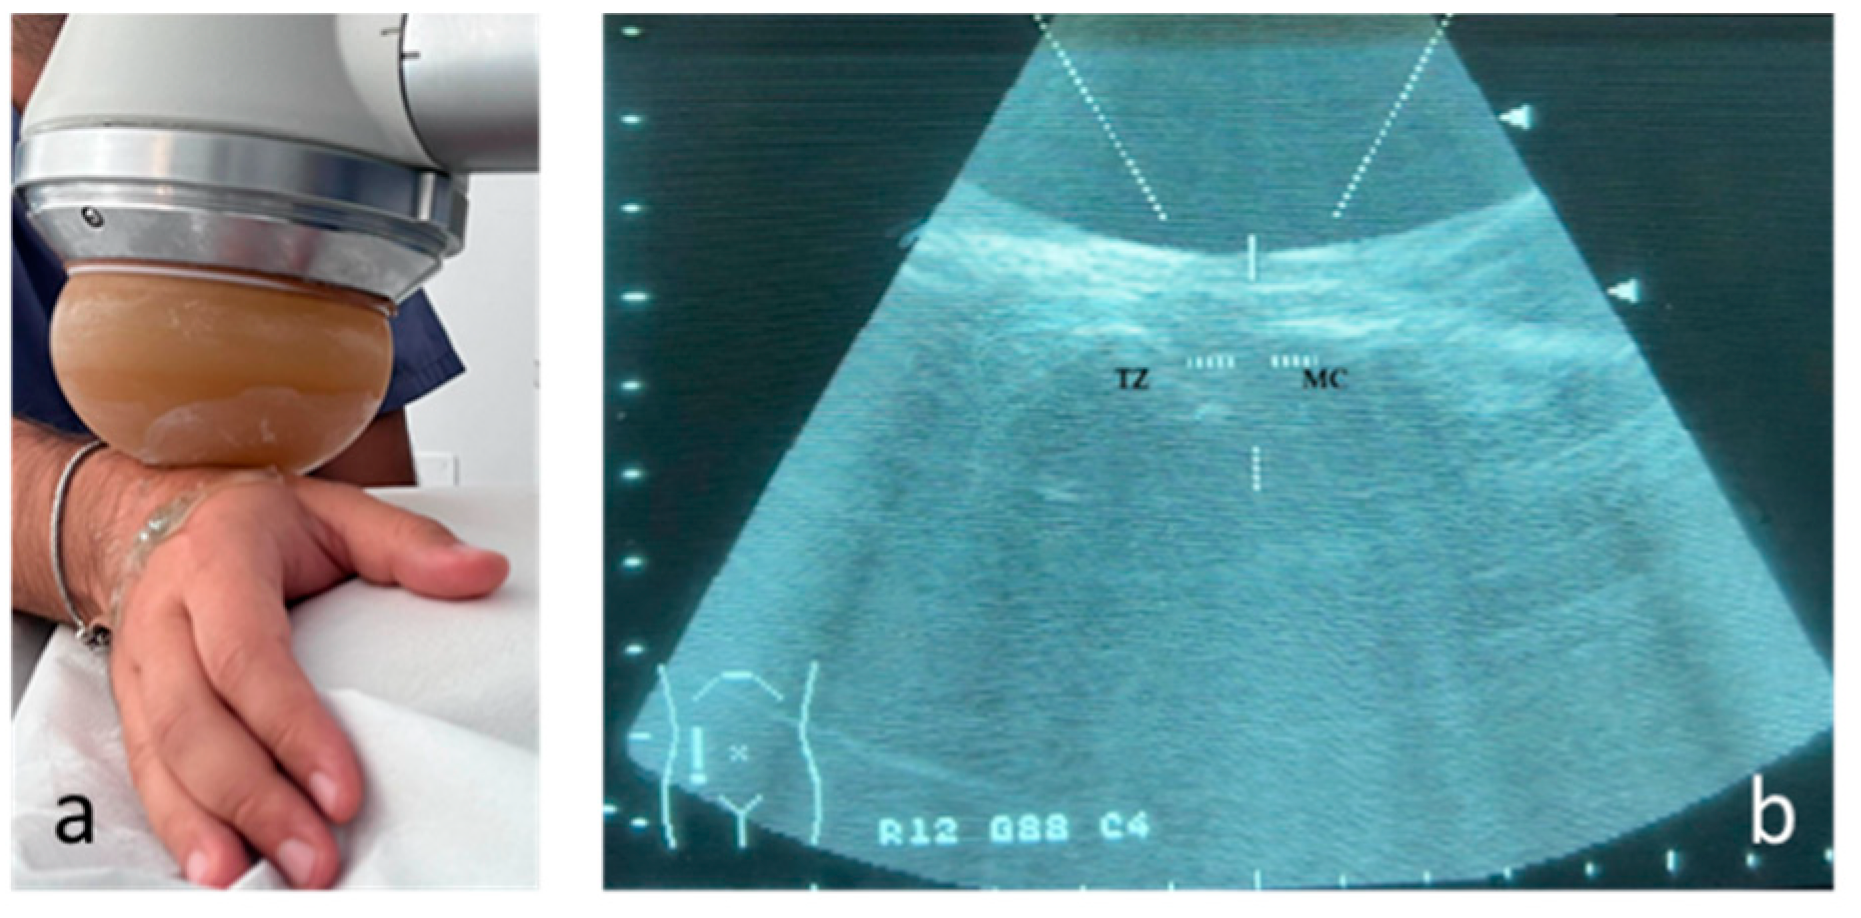

The therapy was applied using a focused shock wave device (Minilith, Storz, Swiss) at the trapezius metacarpal joint, under ultrasound guidance (Figure 1). The shock wave therapy was performed with the patient's hand in intermediate prono-supination and was administered once a week, for 3 sessions. For each treatment session, 2000 pulses were applied with an average energy flux density (EDF) between 0.03 and 0.08 mJ/mm2 and a frequency of 4 pulses per second (4 Hz). Gel was used between the probe and the skin during applications to ensure conductivity. No local anesthetic was used. The protocol was defined in accordance with the literature [12].

Figure 1. Treatment of osteoarthritis of trapezius metacarpal joint during shock wave therapy under ultrasound guidance. The positioning of the probe on the wrist during treatment (a) and ultrasound image of the district according to the long axis (TZ: trapezius; MC: first metacarpal), with the focal area of treatment identified (white cross) (b).